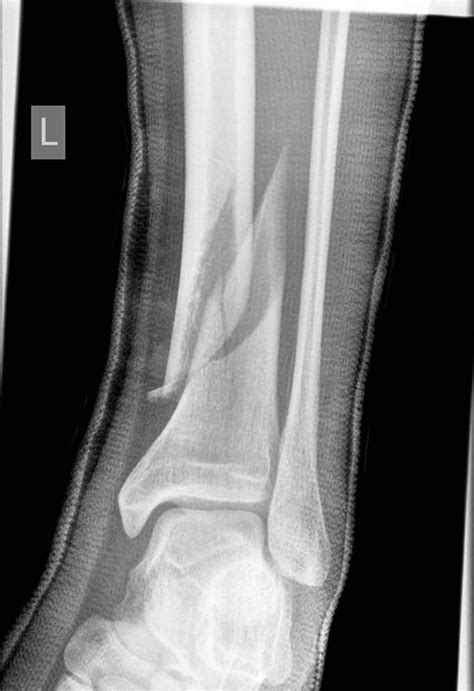

Medical X-ray of a leg

3. Seek medical imaging: Doctors will almost always order an X-ray to determine the exact location and severity of the break.

When you arrive at a clinic or emergency department, the medical team will evaluate your Tibia Fracture Symptoms through a series of diagnostic steps. They will perform a physical examination to check for pulses in the foot and sensory function in the lower leg. Following this, imaging is mandatory. X-rays provide a clear image of the fracture lines and displacement. In more complex scenarios, such as injuries involving the knee or ankle joint, a CT scan may be requested to gain a three-dimensional view of the bone structure.